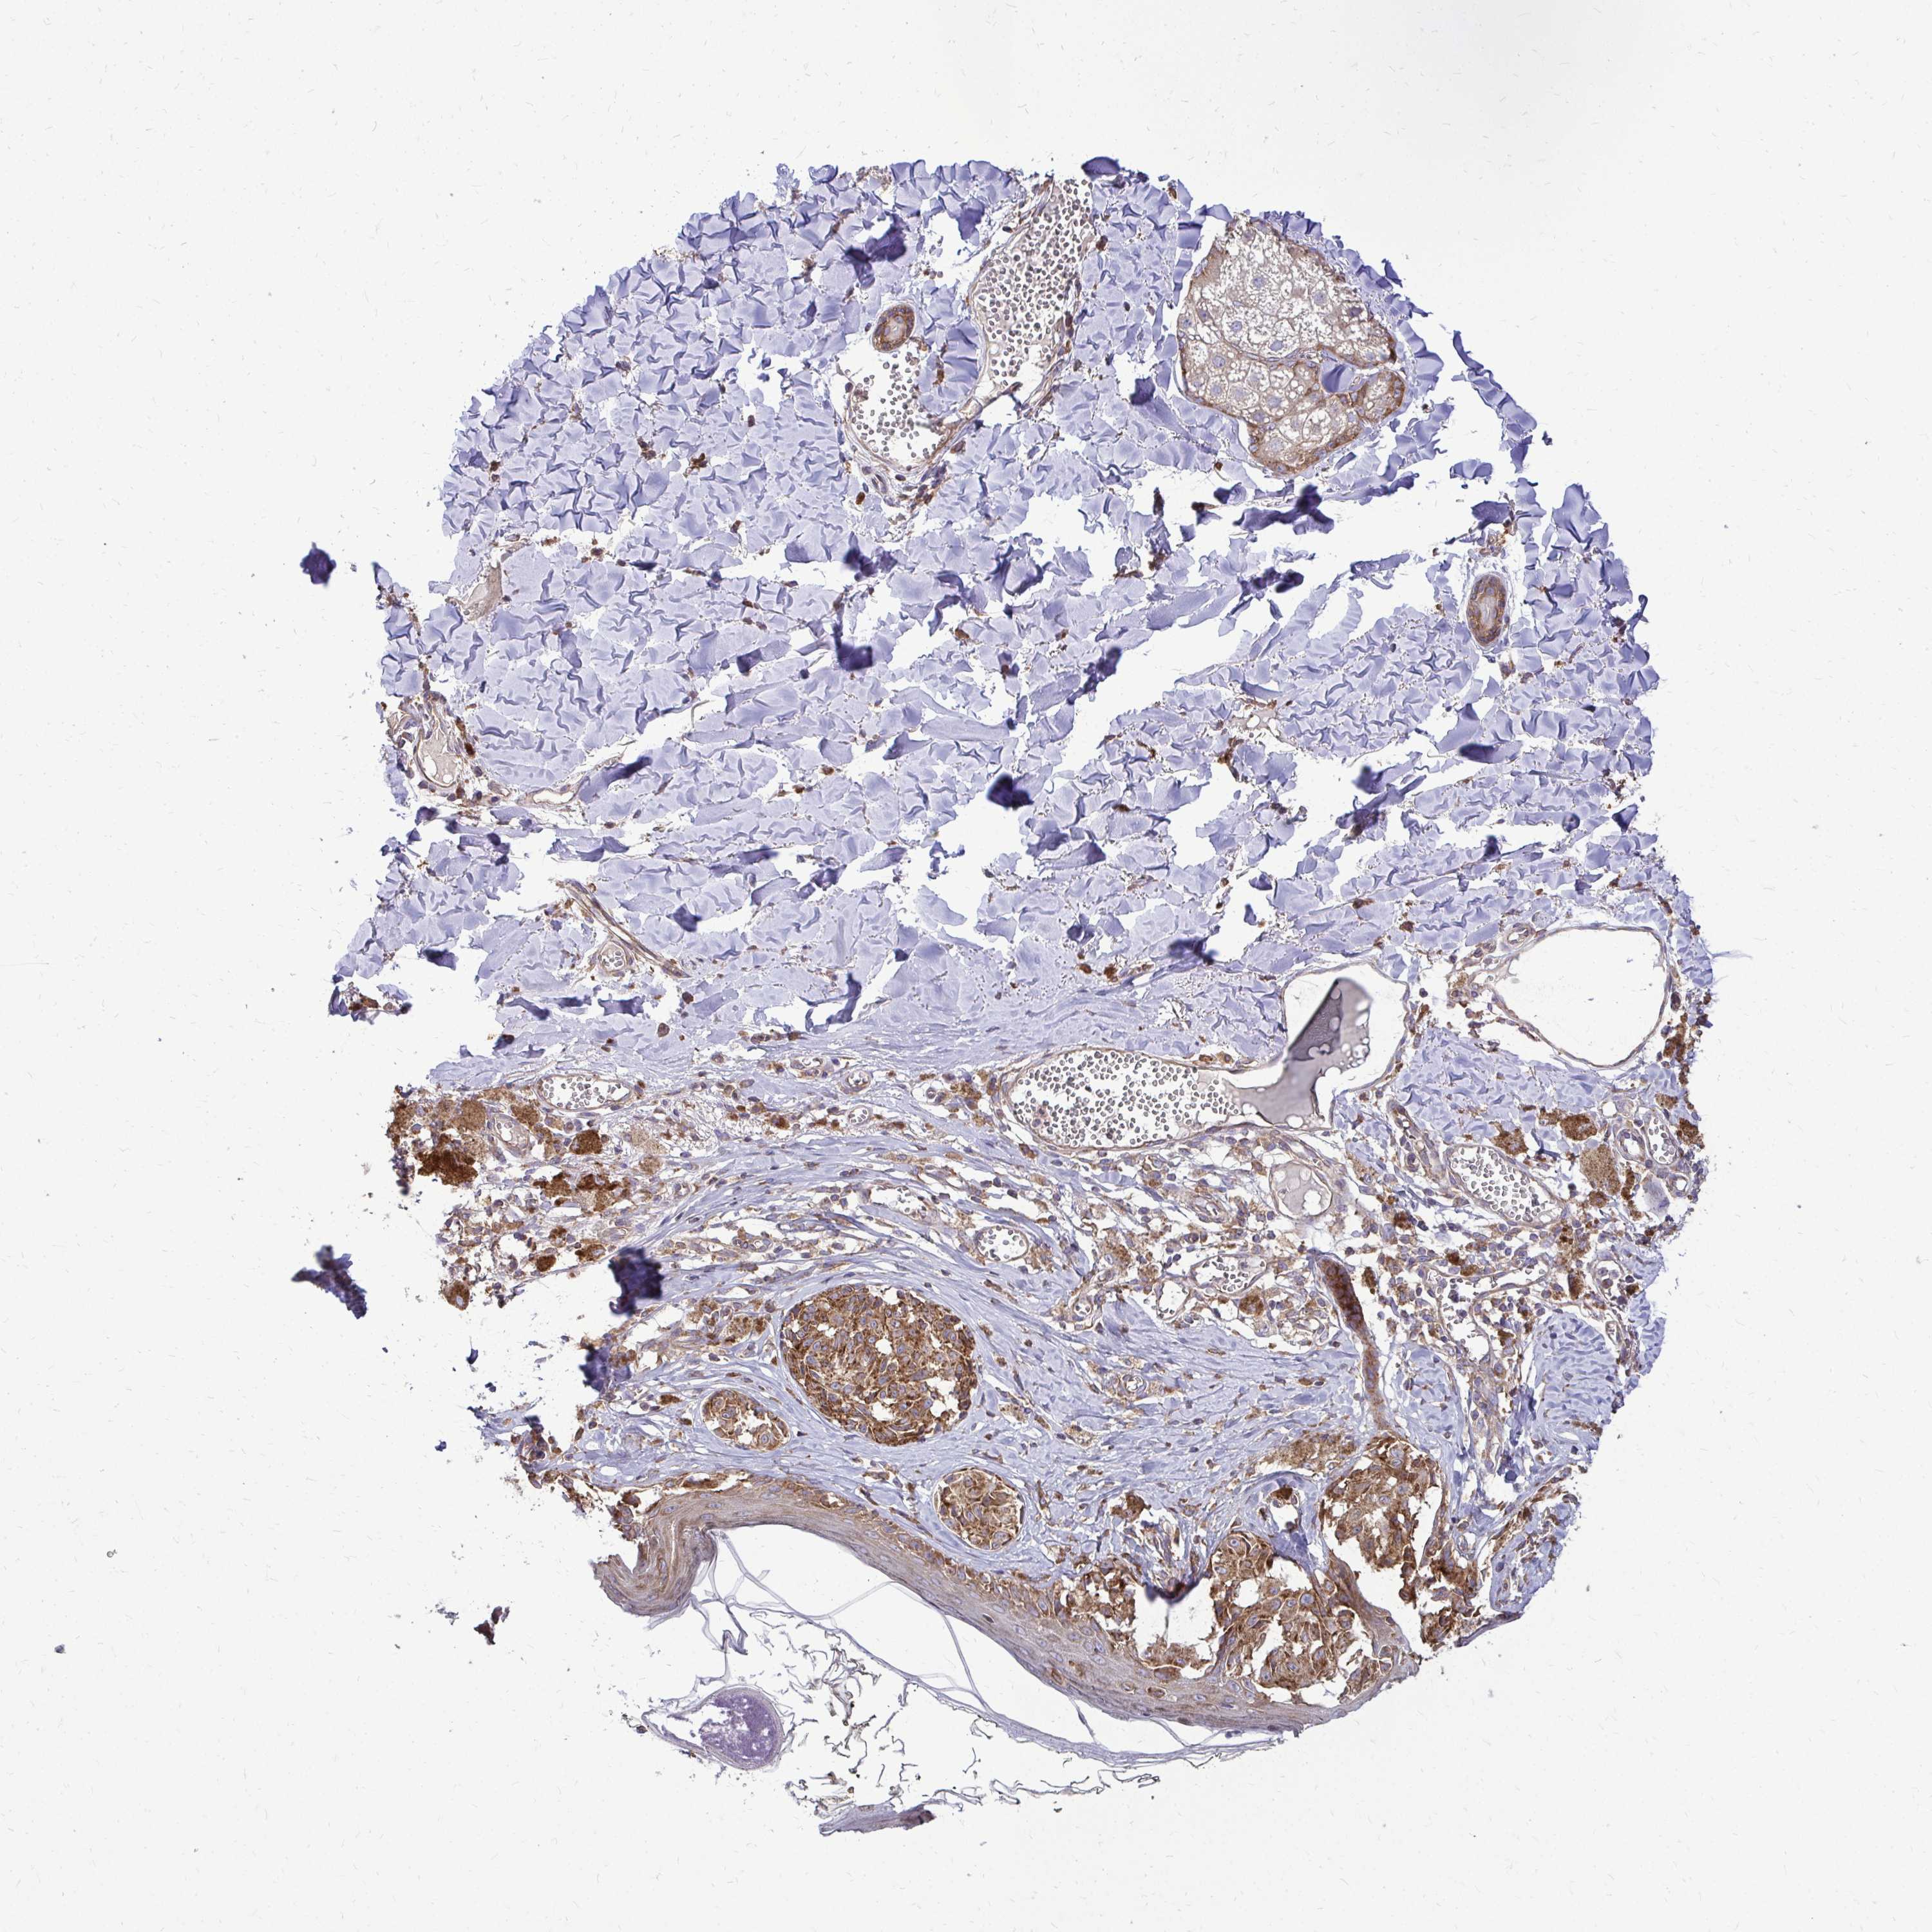

MELANOMA - Protein expressioni

A mouse-over function shows sample information and annotation data. Click on an image to view it in a full screen mode. Samples can be filtered based on level of antibody staining by selecting one or several of the following categories: high, medium, low and not detected. The assay and annotation is described here.

Note that samples used for immunohistochemistry by the Human Protein Atlas do not correspond to samples in the TCGA dataset.

Antibody stainingi

Antibody staining in the annotated cell types in the current human tissue is reported as not detected, low, medium, or high, based on conventional immunohistochemistry profiling in selected tissues. This score is based on the combination of the staining intensity and fraction of stained cells.

Each image is clickable and will lead to virtual microscopy that enables deeper exploration of all samples and also displays staining intensity scores, fraction scores and subcellular localization as well as patient and tissue information for each sample.

Antibody HPA050118

Antibody HPA056084

Antibody CAB012444

Staining

High

Medium

Low

Not detected

Intensity

Strong

Moderate

Weak

Negative

Quantity

>75%

75%-25%

<25%

None

Location

Nuclear

Cytoplasmic/membranous

Cytoplasmic/membranous,nuclear

Malignant melanoma, NOS

Malignant melanoma, Metastatic site